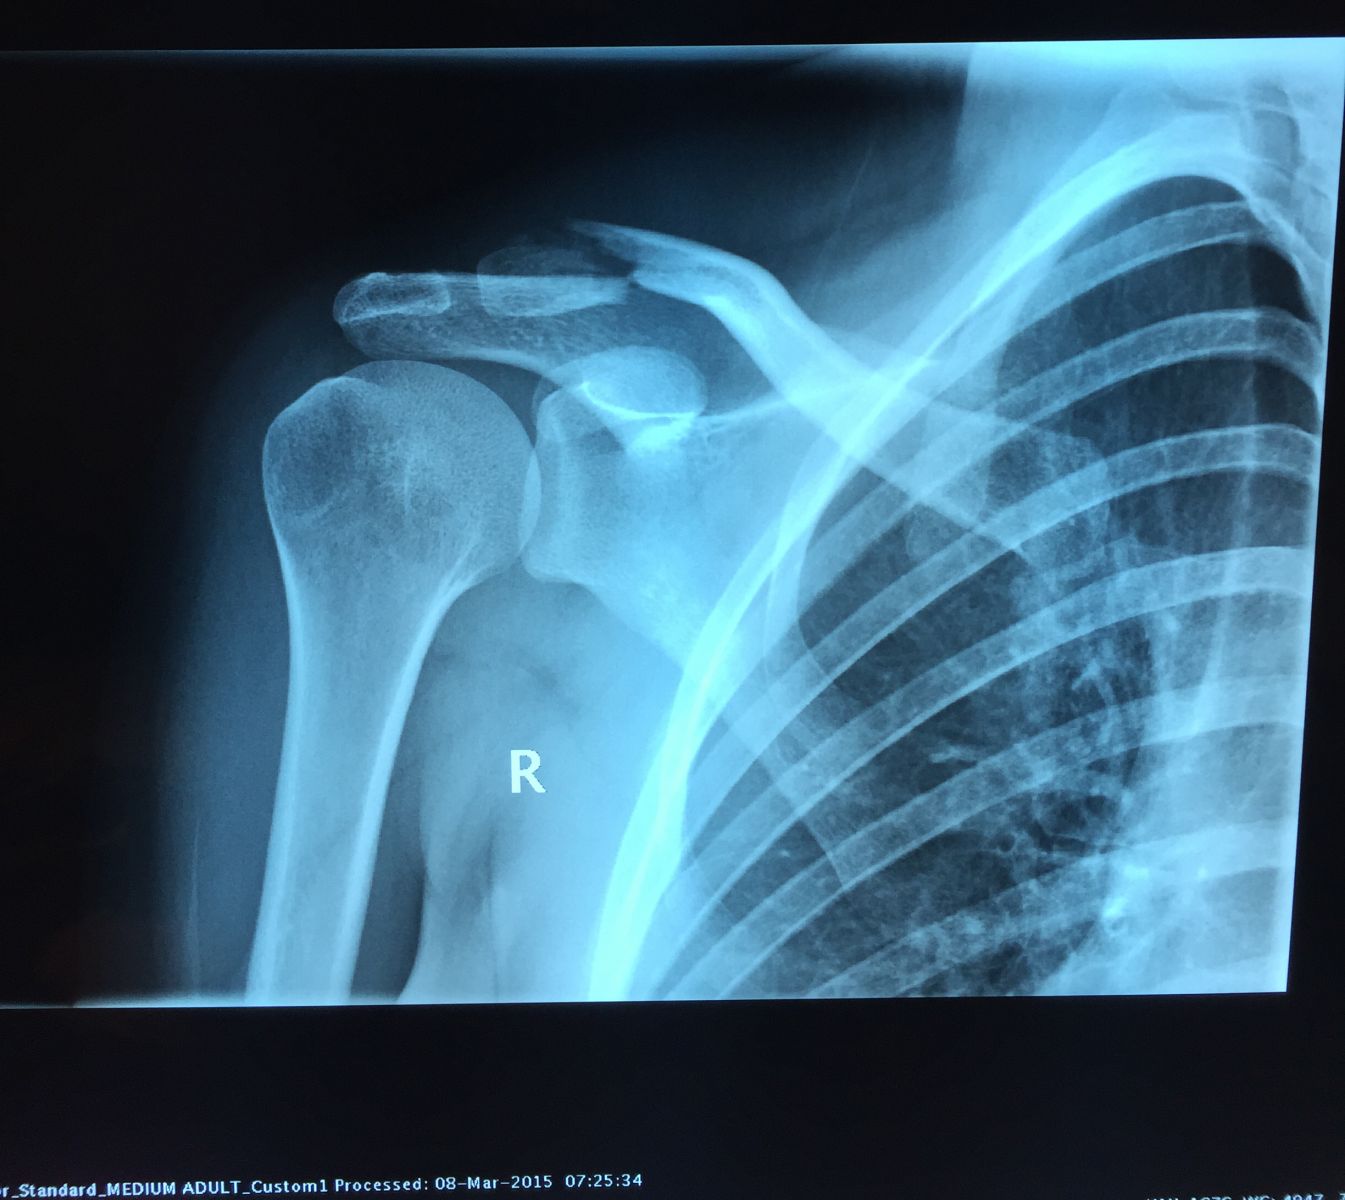

Προεγχειρητικά